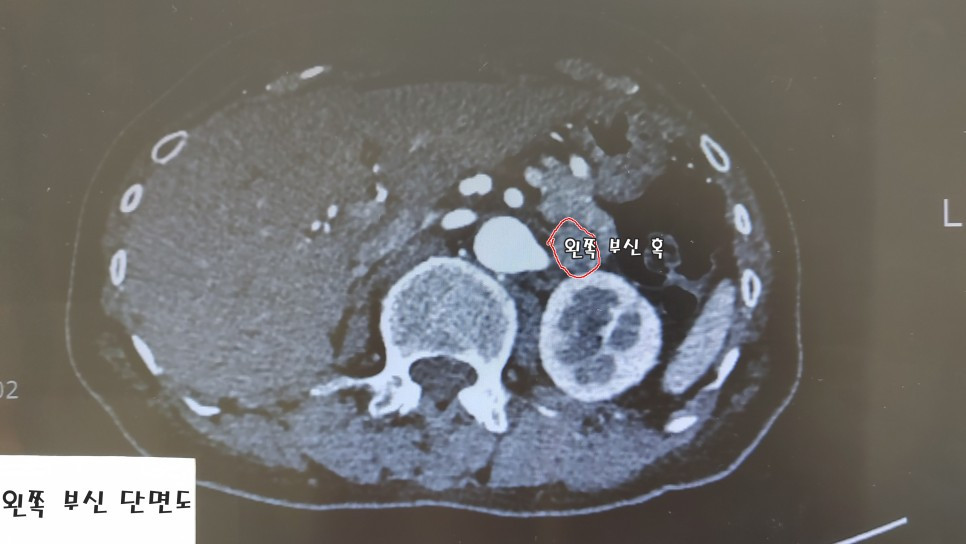

왼쪽 부신이 완전히 망가져 있었다.

오른쪽 부신 대비 50배까지 많은 알도스테론이 분비되고 있었다. 헉!

그동안 불쌍한 내 왼쪽 부신이 아프다고 내게 보낸 신호가 이렇게 온몸 통증으로 전해지나 보다.

결국 내 왼쪽 부신을 품고 살 수 없는 상황이니, 잘라내는 수술을 하게 된다.

혹이 있는 부신이 정상이고, 혹이 없는 부신에서 알도스테론이 많이 나올 때,

다행히 나는 혹 있는 왼쪽 부신이 비정상이고, 오른쪽 부신은 정상임이 정맥 채혈로 확인됐다.